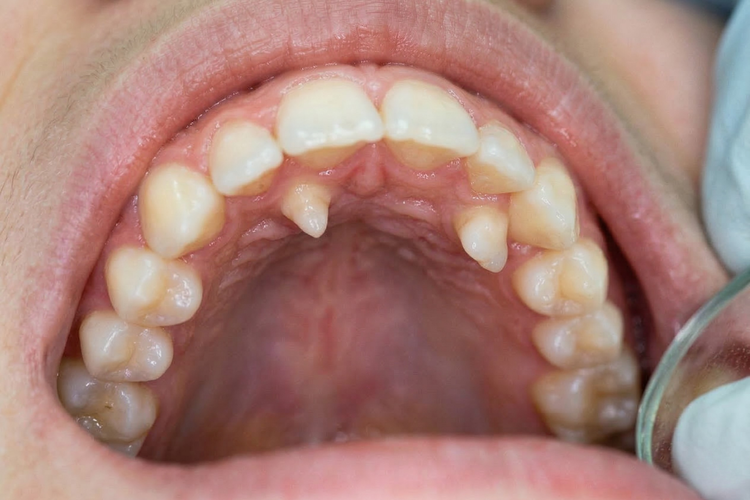

Intraoral view showing mesiodens supernumerary teeth behind the front teeth.

Mesiodens Develops between the two upper central incisors (the two front teeth). May cause spacing, rotation, or delayed eruption of permanent front teeth.